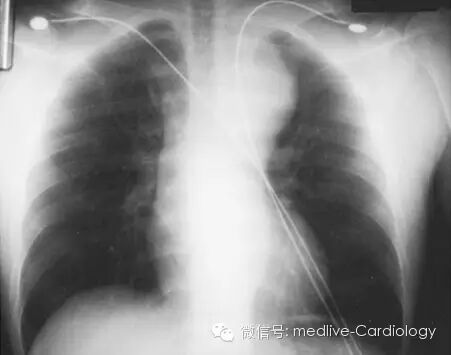

在诊断主动脉夹层的过程中,胸片常作为第一项影像学检查,虽然它敏感性和特异性均不高。如下图所示,纵膈影增宽是最常见的表现,特别是在升主动脉夹层的患者中更为常见。其它的表现包括双重主动脉结、主动脉壁钙化影内移、气管右移、心包积液、心影增大、左肺尖模糊、主动脉轮廓不规则、胸腔积液。

如果主动脉夹层破裂,血液会外渗到同侧胸膜腔中,导致血胸形成。如下图所示,大量血胸在胸片上会表现为同侧全肺野透过度减低。